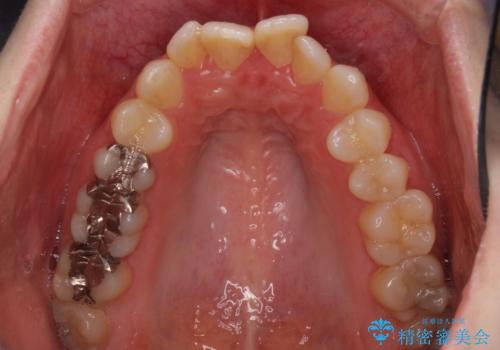

- 前歯のデコボコを気にして来院された患者様です。

下顎が骨格的にずれており、上下正中を合わせることは難しいことが予想されたため、デコボコの解消を主目的として、ワイヤー矯正を行うこととしました。

治療途中で出産されたこともあり、当初予定よりも終了までに期間がかかってしまいました。

舌を前方に突出する癖があったため、上下前歯がなかなか接触しなかったことも治療期間が伸びた要因です。